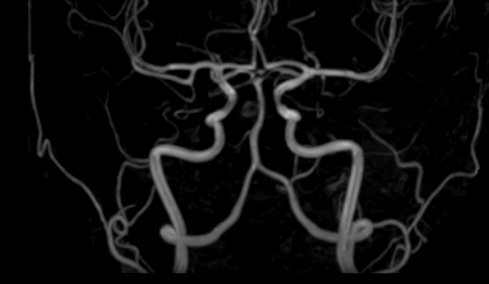

Стандартная МРТ головного мозга дает важную информацию о состоянии и структуре мозговой ткани для выявления большого числа заболеваний, в том числе опухолевых образований, демиелинизирующих заболеваний, воспалительных процессов головного мозга и мозговых оболочек. Стандартную МРТ головного мозга дополняет МР-ангиография, которая отображает состояние артериальной системы кровоснабжения головного мозга. МР-венография головного мозга позволяет детально изучить особенности анатомического и функциональной состояния венозного русла головного мозга.

Компьютерная программа обрабатывает данные, полученные при сканировании, и формирует объемные изображения как самого мозга, так и сосудистой системы в отдельности без прилегающих тканей. Обе методики применяются одновременно и взаимодополняют друг друга, давая полную диагностическую картину.